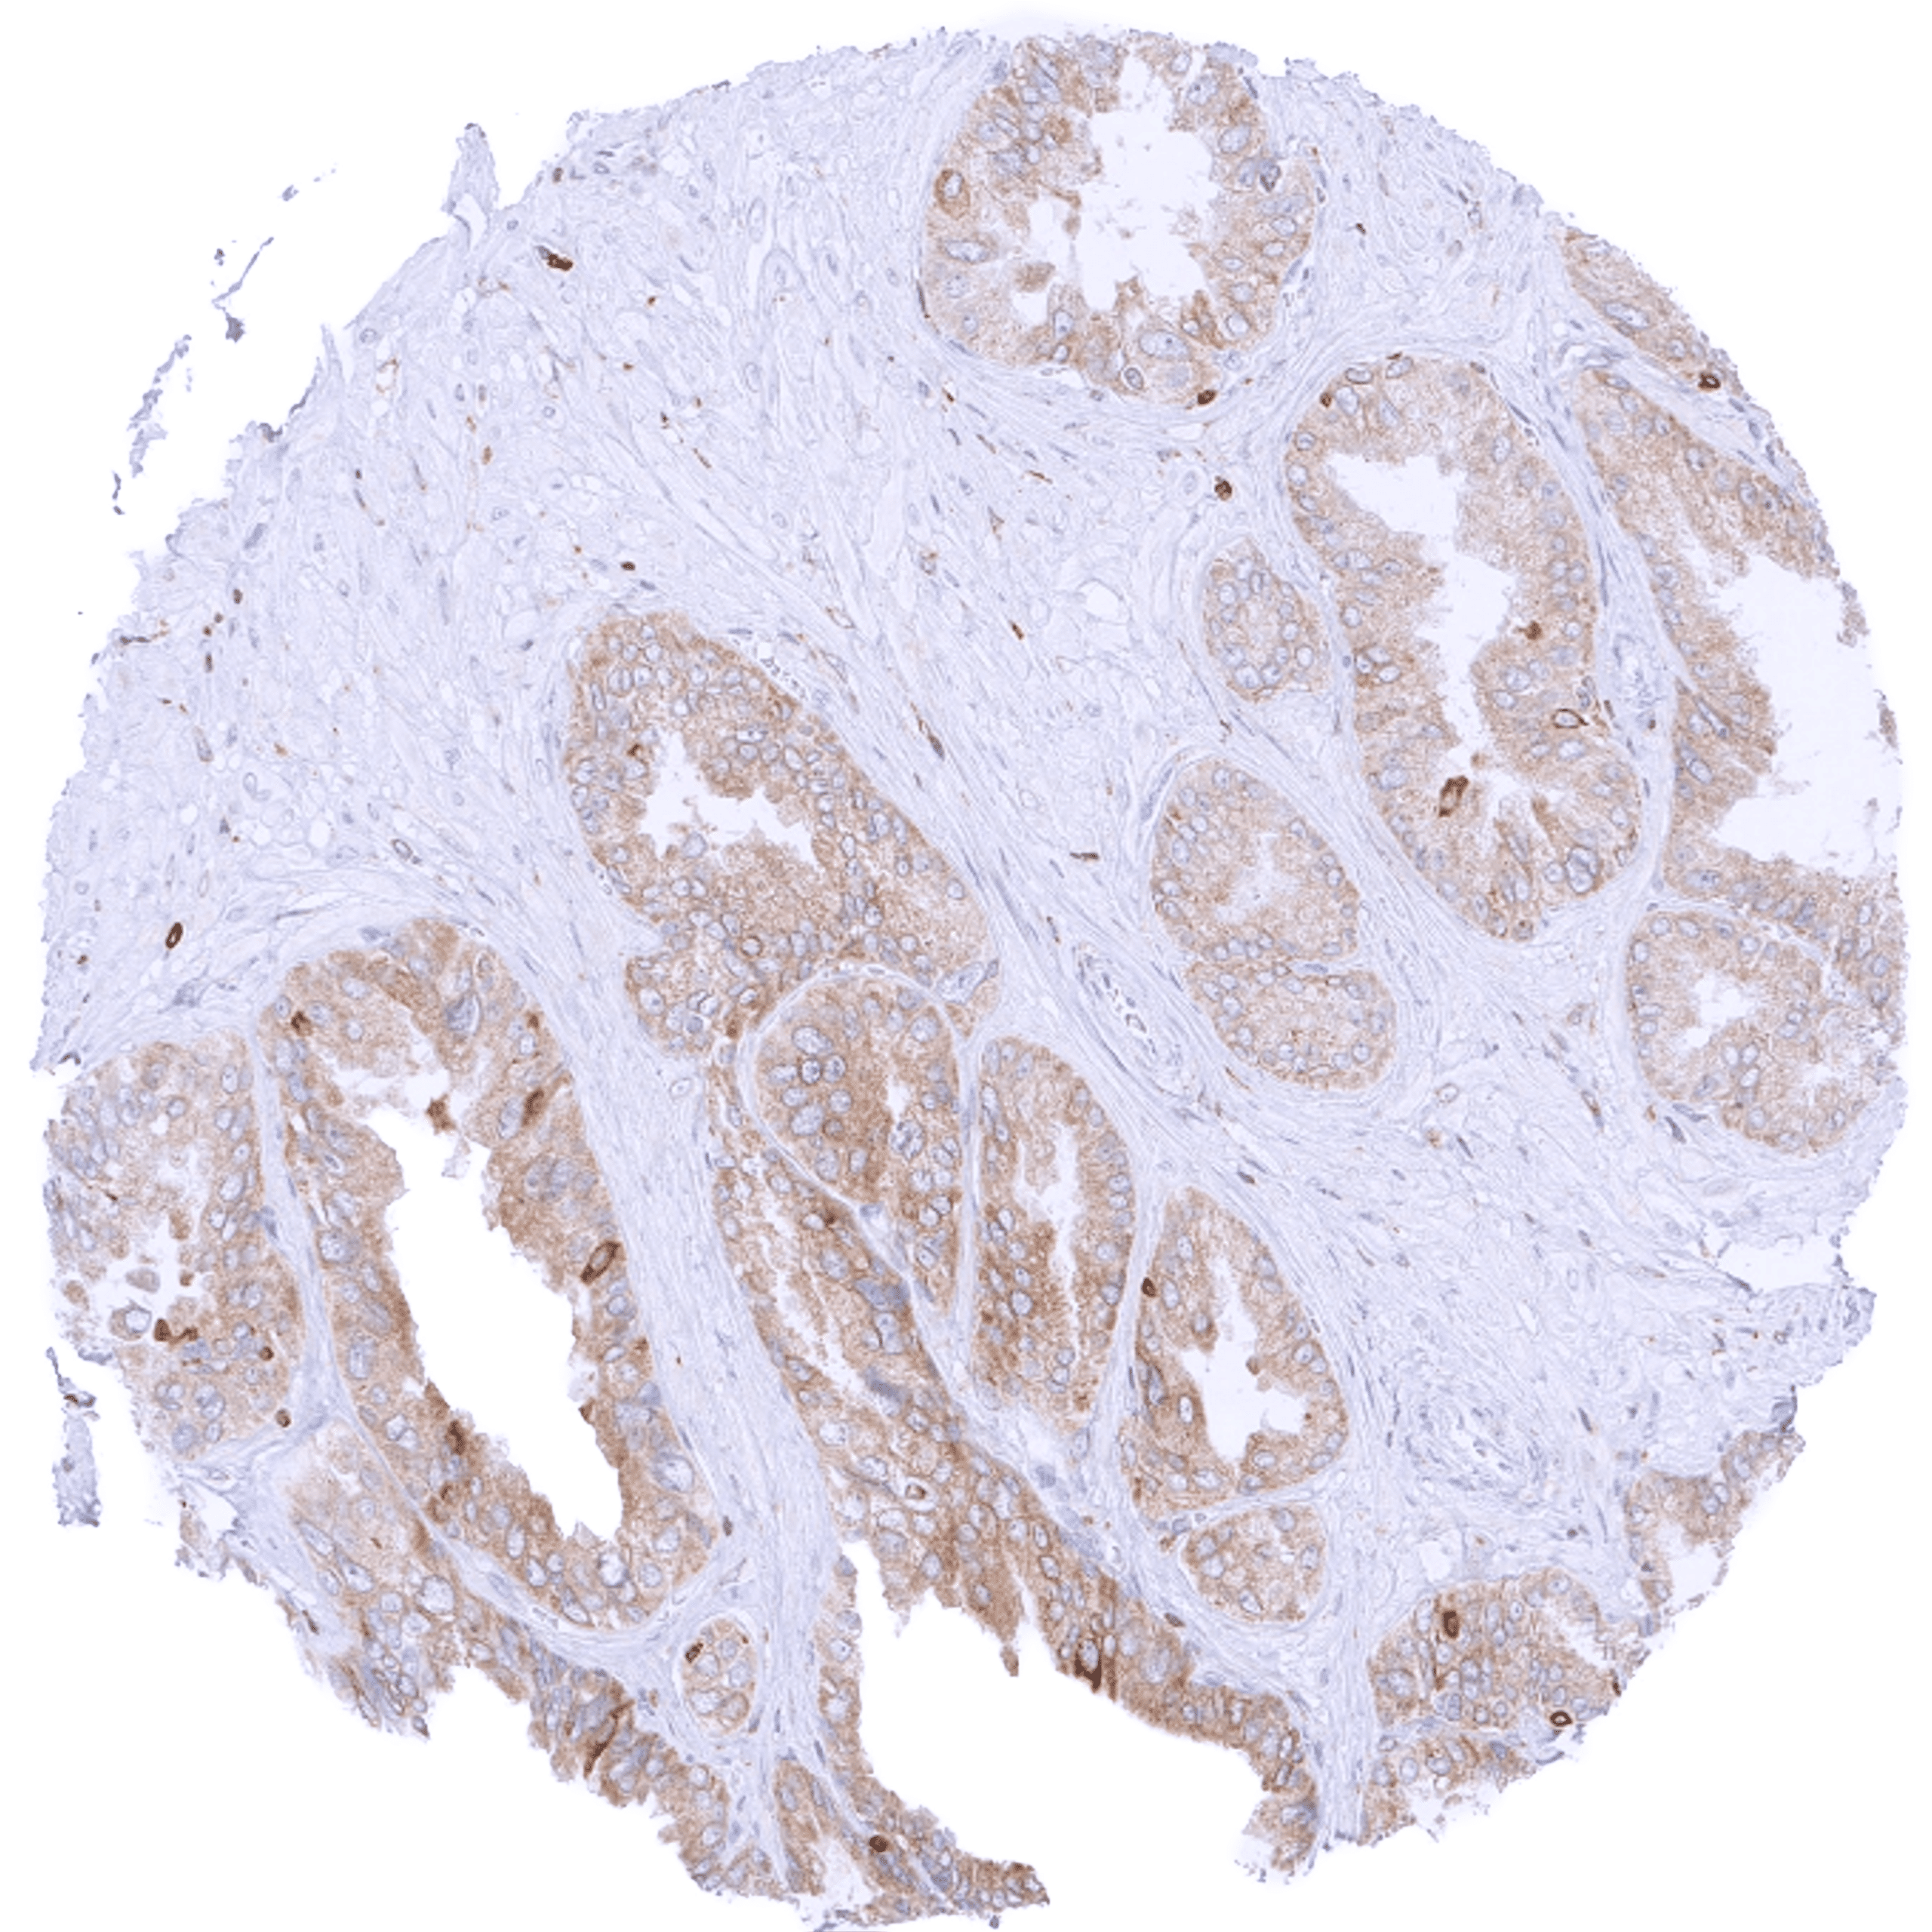

| Male genital | Prostate | Weak to moderate bcl-2 staining of basal cells. |